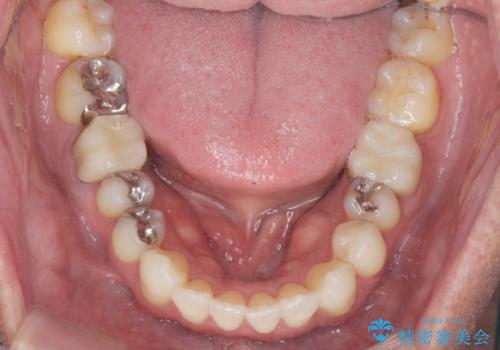

- 突き出た前歯の角度の改善と虫歯治療の改善を求めて来院されました。

虫歯を除去したのち、マウスピース矯正治療を行い、歯並びやがたつきを改善したのち、セラミックに置き換えることで審美性の向上を計画します。